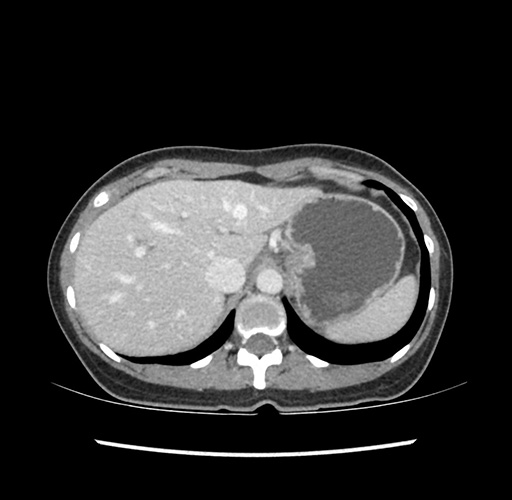

Imaging Analysis

Look through the patient's CT scan to identify any areas of concern for the necessary procedure.

Based on your CT findings, which issue(s) would give reason for "planned slowing down moment(s)" in this case?

Considering a standard left lateral sectionectomy procedure, what step(s) of the operation would you do differently in this case ?